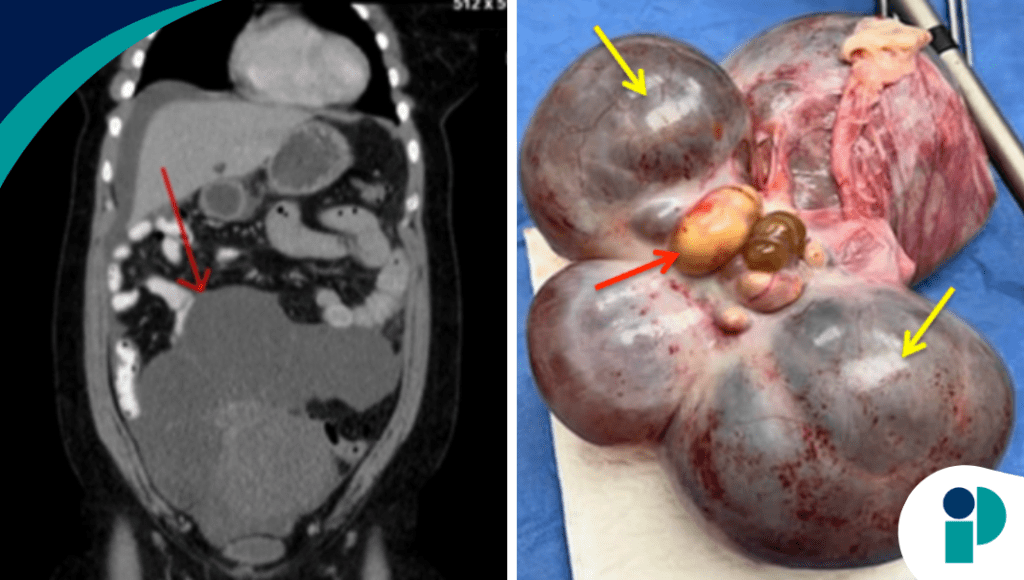

El diagnóstico definitivo se estableció tras la cirugía y el estudio histopatológico, que confirmó struma ovarii, un tipo de teratoma ovárico compuesto principalmente por tejido tiroideo. Aunque generalmente es benigno, su presentación clínica puede ser indistinguible de un cáncer ovárico.

Tras el manejo quirúrgico adecuado, se observó resolución de la ascitis y del derrame pleural, lo cual es característico del pseudo-Meigs y confirma la naturaleza benigna del proceso.